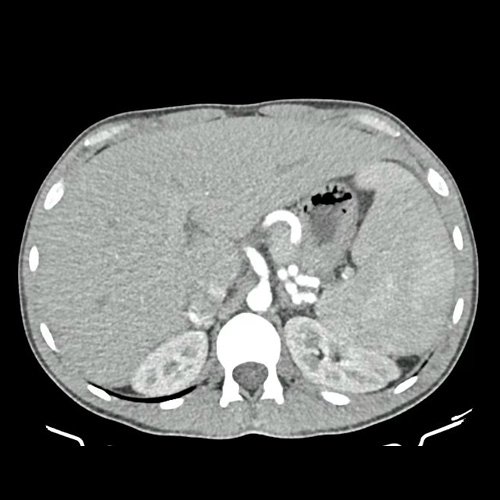

• TAC de Tórax (23/10/24): Escaso derrame pleural bilateral. No se visualiza imagen sugerente de Neumopatía.

TAC de abdomen corte axial previas 22/11/24